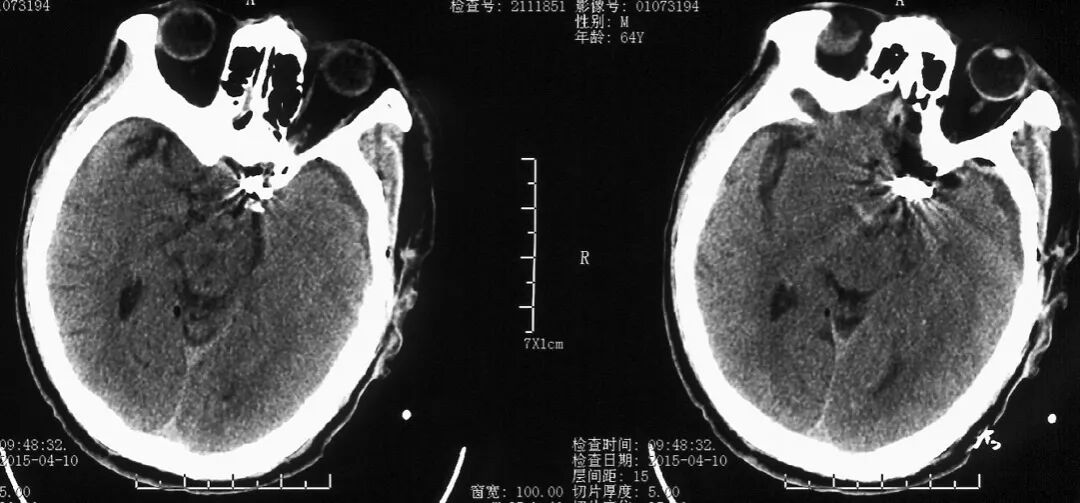

术前头颅CT检查(发病6天后)

头颅CT可见鞍区类圆形高密度影

(黄色箭头示)